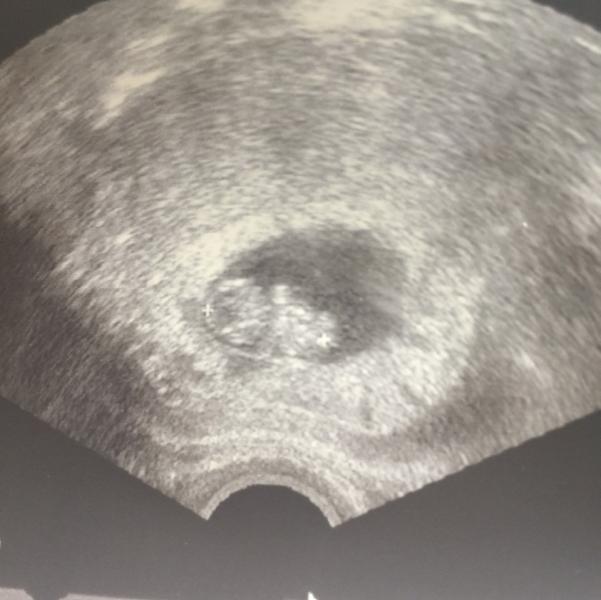

ой лапуся такой,скоро и у меня такой будет уже, принесла фото где нам 7 недель, показываю мужу где головка,где хвостик будет,он спрашивает -как ты видишь?, это наверное наше,материнское 💖💖💖

@evoshkina, не у всех) у нас наоборот папа всё увидел, а по мне - так это был банан с головой))))